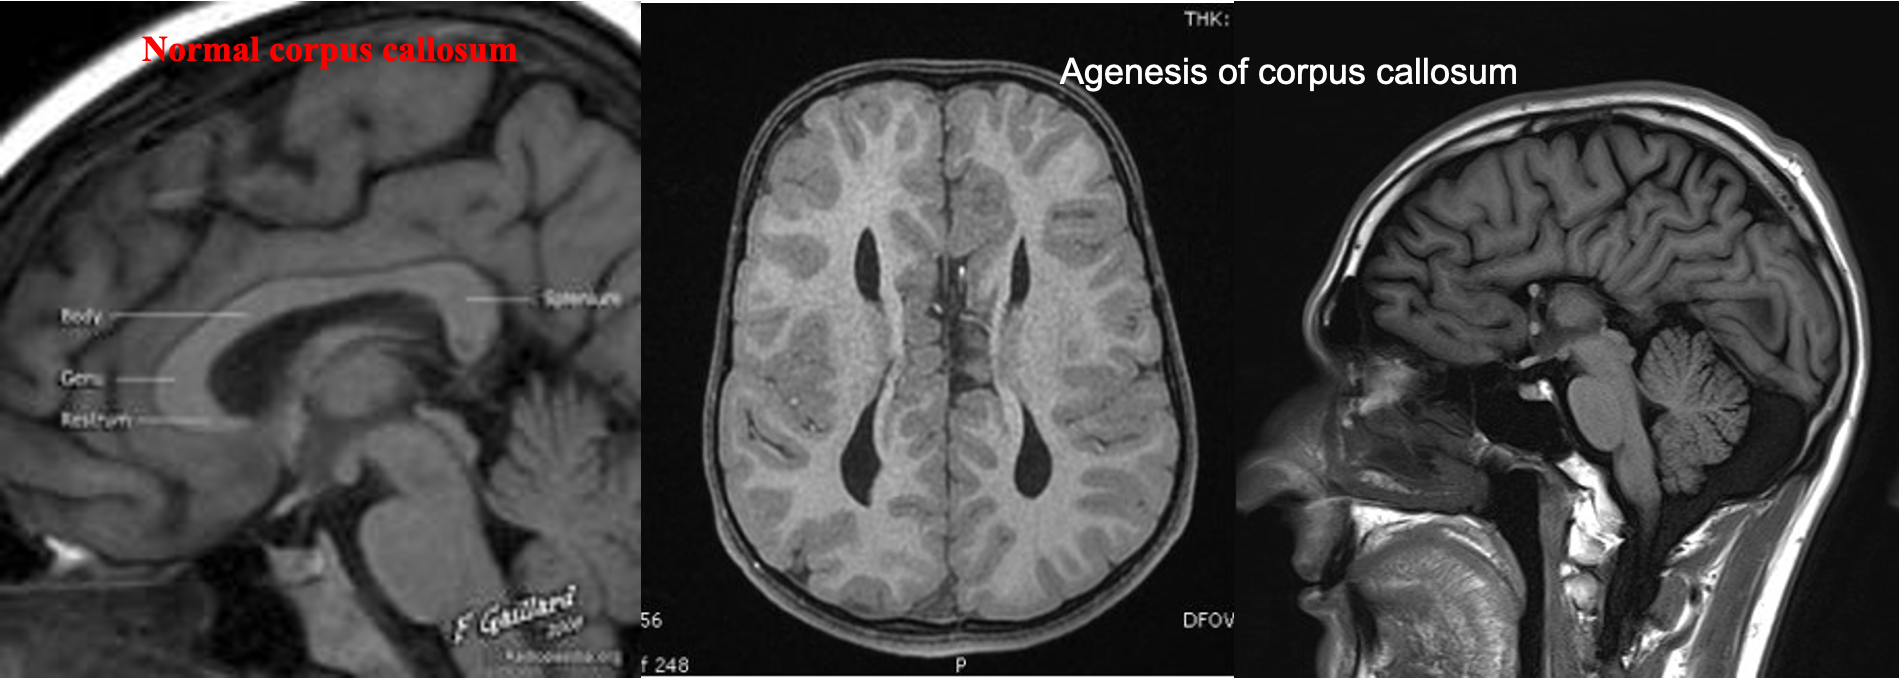

CCA :On axial views, the ventricles appear similar to a racing car (Parallel configuration of the lateral ventricles )